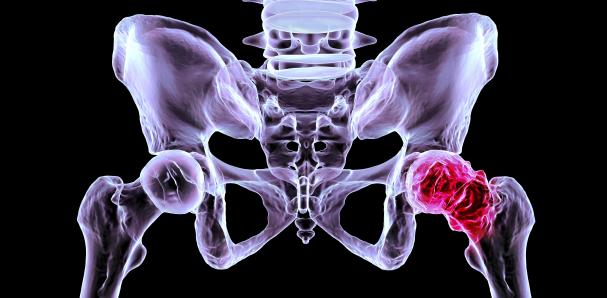

Un estudio liderado por investigadores de la Universidad de Stanford revela el papel clave de la proteína 15‑PGDH en la destruccïón del cartílago articular durante la Artrosis. Según el informe publicado por La Vanguardia este lunes, al inhibir esa proteína con un fármaco experimental, fue posible restaurar cartílago dañado en rodillas de ratones y en muestras humanas.

El hallazgo representa un cambio radical de paradigma: la artrosis, una enfermędad degenerativa que afęcta a millones de personas de todo el mundo y hoy solo puede aliviarse con analgésicos, fisioterapia o prótesis, podría tener por fin un tratamiento capaz de revertir el däño de raíz.

En los experimentos con roedores, la terapia logró regenerar cartílago hialino, el tipo de tejido que caracteriza a la articulación sana, no fibrocartílago de menor calidad como en métodos anteriores. Además, los animales recuperaron la movilidad y la capacidad de carga en las articulaciones tratadas, lo que sugiere alivio del dølor y recuperación funcional.

Lo más sorprendente: la regeneración no requirió de células madre. El fármaco reactivó células del propio cartílago que estaban “silenciadas”, induciendo la reparación del tejido däñado. Esa vía, menos inväsiva, más natural, podría marcar el camino para una nueva generación de terapias para artrosis.

Aunque aún en fase experimental, los primeros ensayos clínicos con personas ya están en marcha, inicialmente para tratar pérdida muscular por envejecimiento, y los investigadores planean extenderlos a pacientes con artrosis. Si todo sigue su curso, esta terapia podría convertirse en la primera capaz de revertir osteoartrosis en humanos.